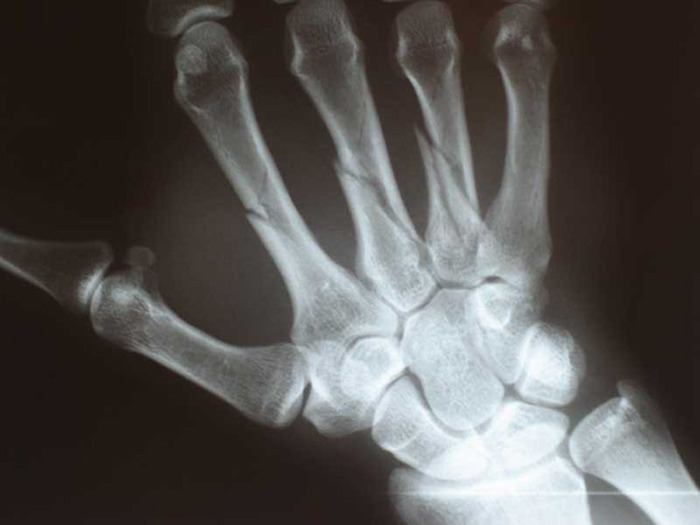

Image: Courtesy of JVinocur. Metacarpal Fractures.

Now, you can grow new bone inside your body. University of Iowa researchers have created a “bio patch” that regenerates bone tissue.

It has been demonstrated to completely regrow bone in mouse test subjects and to stimulate growth in human cells, as reported in Biomaterials.

The team, led by Satheesh Elangovan, used microscopic plasmid particles, embedded with pieces of DNA specifically related to producing growth. They delivered bone-producing instructions to existing bone cells inside a living body. The bone cells then followed these instructions and began to produce the required proteins for more bone production.

In order to grow the new bone as a perfect fit, researchers made a collagen scaffold in the desired shape, loaded it with the plasmid particles, and inserted it in the target area, where the repair would take place. The bone was completely regenerated in a healthy, normal shape in about four weeks. The biopatch was also able to stimulate new growth in human bone marrow stromal cells.

Imagine what this patch might do to help repair bone injuries and deformities. Birth defects involving missing bone around the head or face and dental applications, such as rebuilding jaw bone to prevent tooth loss or support implants, are just a few of the exciting possibilities.